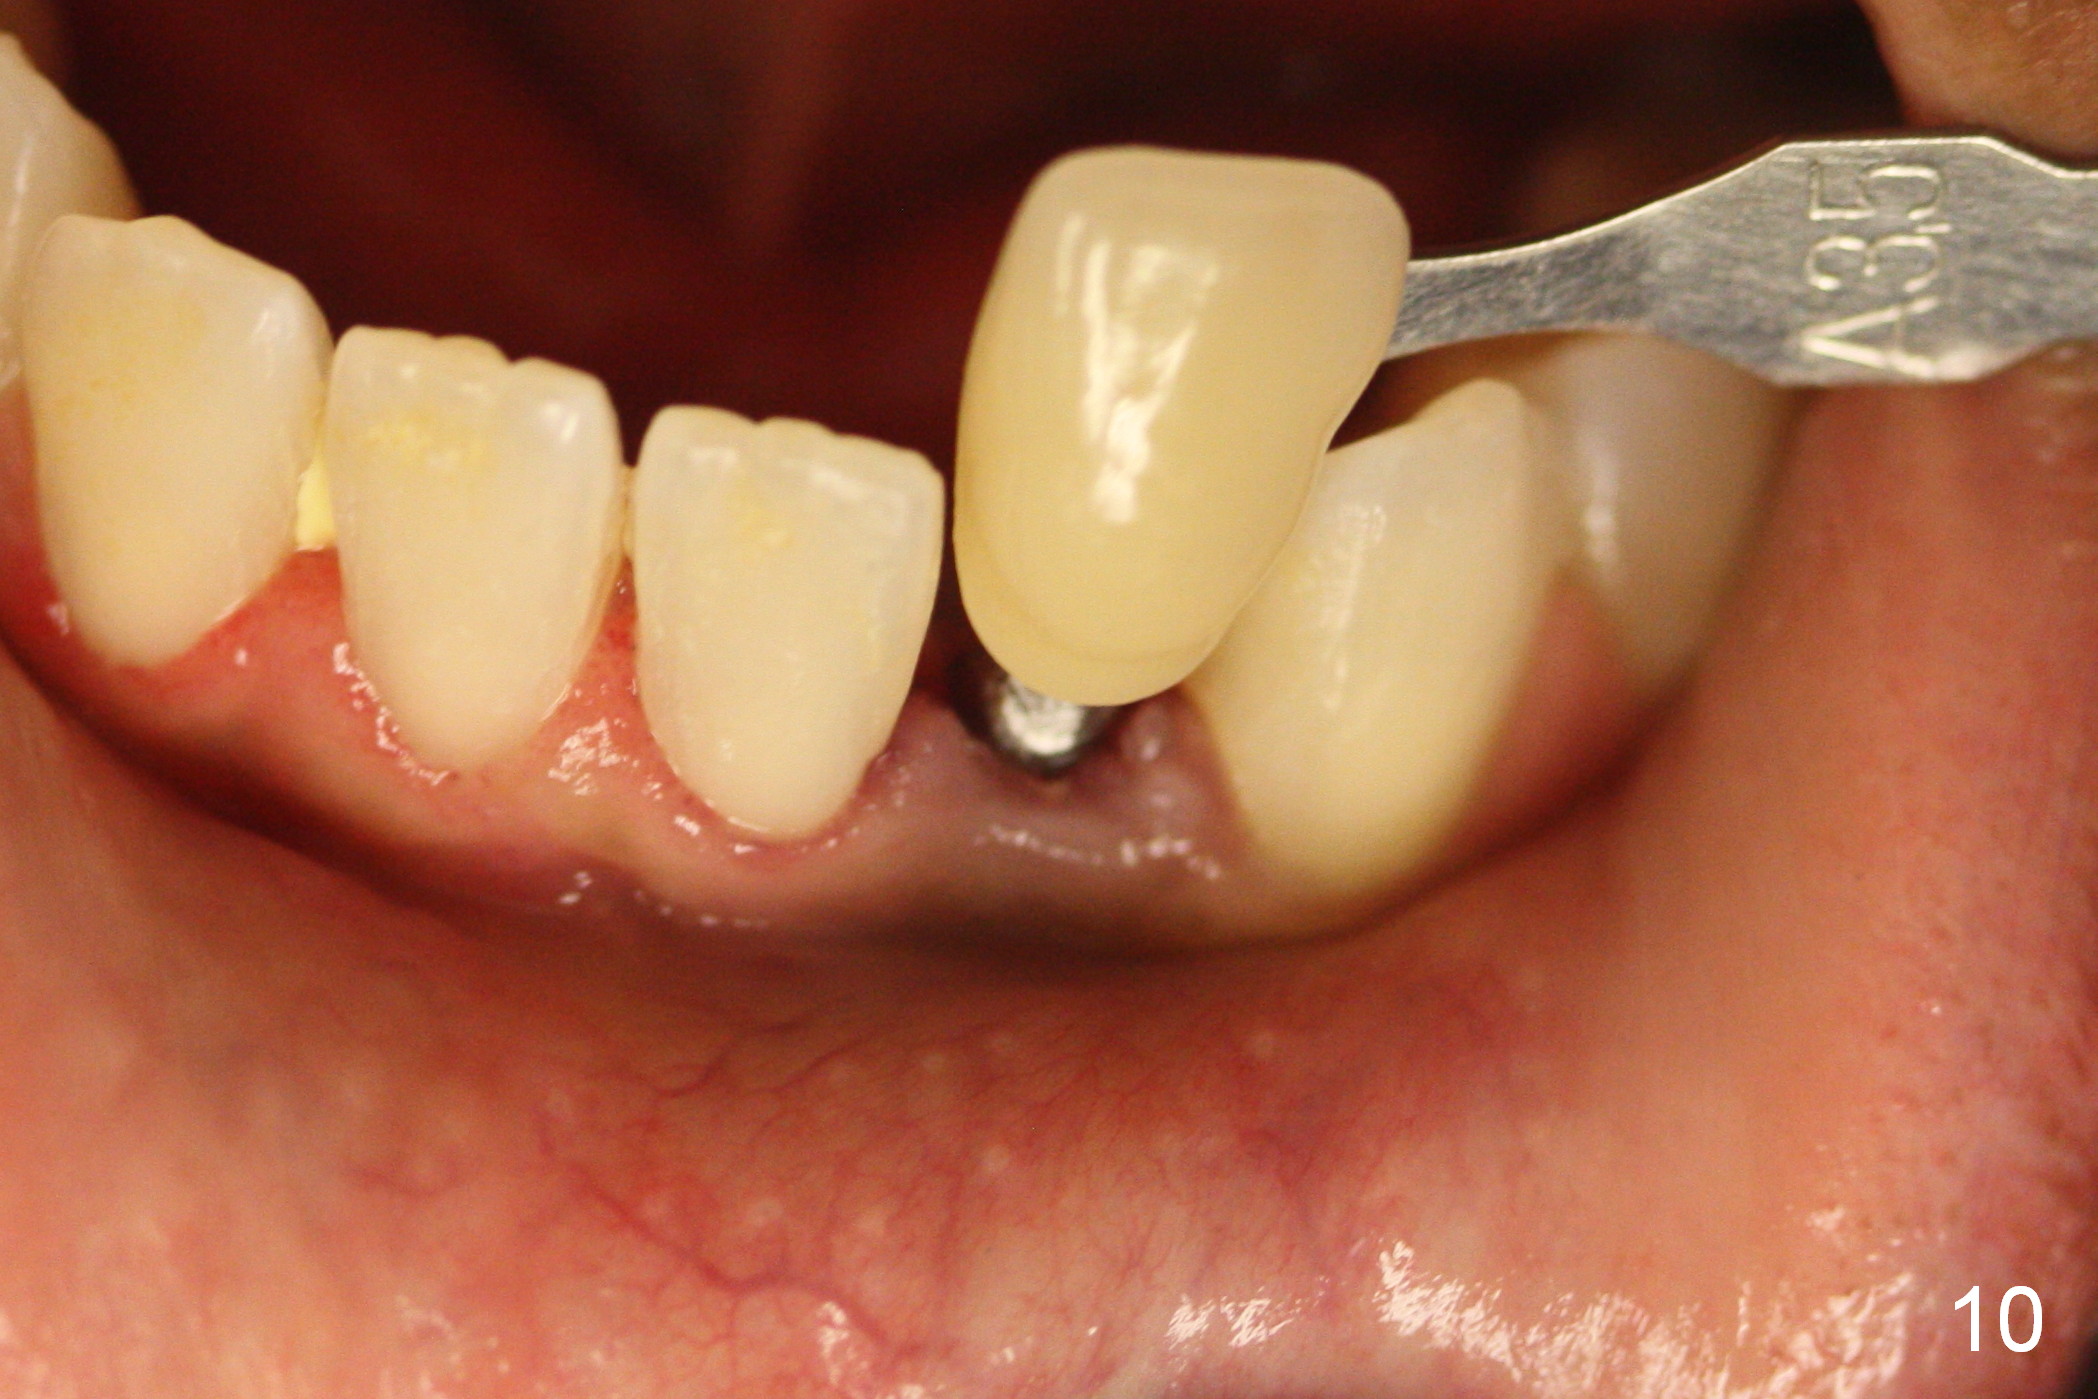

Suggestions for #23 implant crown redo (Fig.1, 2)

has been placed for 2 years 8 months.

It has already osteointegrated.

The buccal surface of the abutment has been further reduced prior to final impression (the previous cast is enclosed in the case).